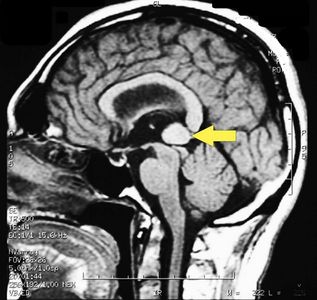

|[[File:Pineal_cavernoma_pre_surgery_2. | |[[File:Pineal_cavernoma_pre_surgery_2.jpg|alt=|center|frameless|180x180px]]<math>\gamma_5=</math> Cavernoma Pineale | ||

|'''Question 5:''' La conclusione dell'iter come già descritto depone per un Cavernosa Pineale molto difficile da aggredireper la sua posizione anatomica. Il paziente fu indirizzato ad un Centro specialistico in neurochirurgia di Verona dal Prof. Albino Bricolo che riesci attraverso un intervento endoscopico ad eliminare la malformazione vascolare e restituire al nostro caro paziente 'Bruxer' una dignitosa vita senza bite plane odontoiatrico. | |'''Question 5:''' La conclusione dell'iter come già descritto depone per un Cavernosa Pineale molto difficile da aggredireper la sua posizione anatomica. Il paziente fu indirizzato ad un Centro specialistico in neurochirurgia di Verona dal Prof. Albino Bricolo che riesci attraverso un intervento endoscopico ad eliminare la malformazione vascolare e restituire al nostro caro paziente 'Bruxer' una dignitosa vita senza bite plane odontoiatrico. | ||

MRI of the brain, using Turbo Spin Echo, Fluid Attenuated Inversion Recovery, and Gradient Echo sequences, was conducted before and after intravenous administration of contrast medium. Results showed the presence of a roundish area of approximately 1.5 cm in diameter located in the vicinity of the quadrigeminal cistern at the level of the pineal gland. There was also a slight dilation of the supratentorial ventricular system, which appeared in the axis and was most evident in the proximity of the temporal horns, with a periventricular rim with a transependymal fluid absorption phenomenon.[1] The signal characteristics of the formation suggested a provisional diagnosis of pineal cavernoma. (Figure 2 and 3)

| Cavernoma Pineale | Question 5: La conclusione dell'iter come già descritto depone per un Cavernosa Pineale molto difficile da aggredireper la sua posizione anatomica. Il paziente fu indirizzato ad un Centro specialistico in neurochirurgia di Verona dal Prof. Albino Bricolo che riesci attraverso un intervento endoscopico ad eliminare la malformazione vascolare e restituire al nostro caro paziente 'Bruxer' una dignitosa vita senza bite plane odontoiatrico. | ||||||||||||||||||||||||||||||